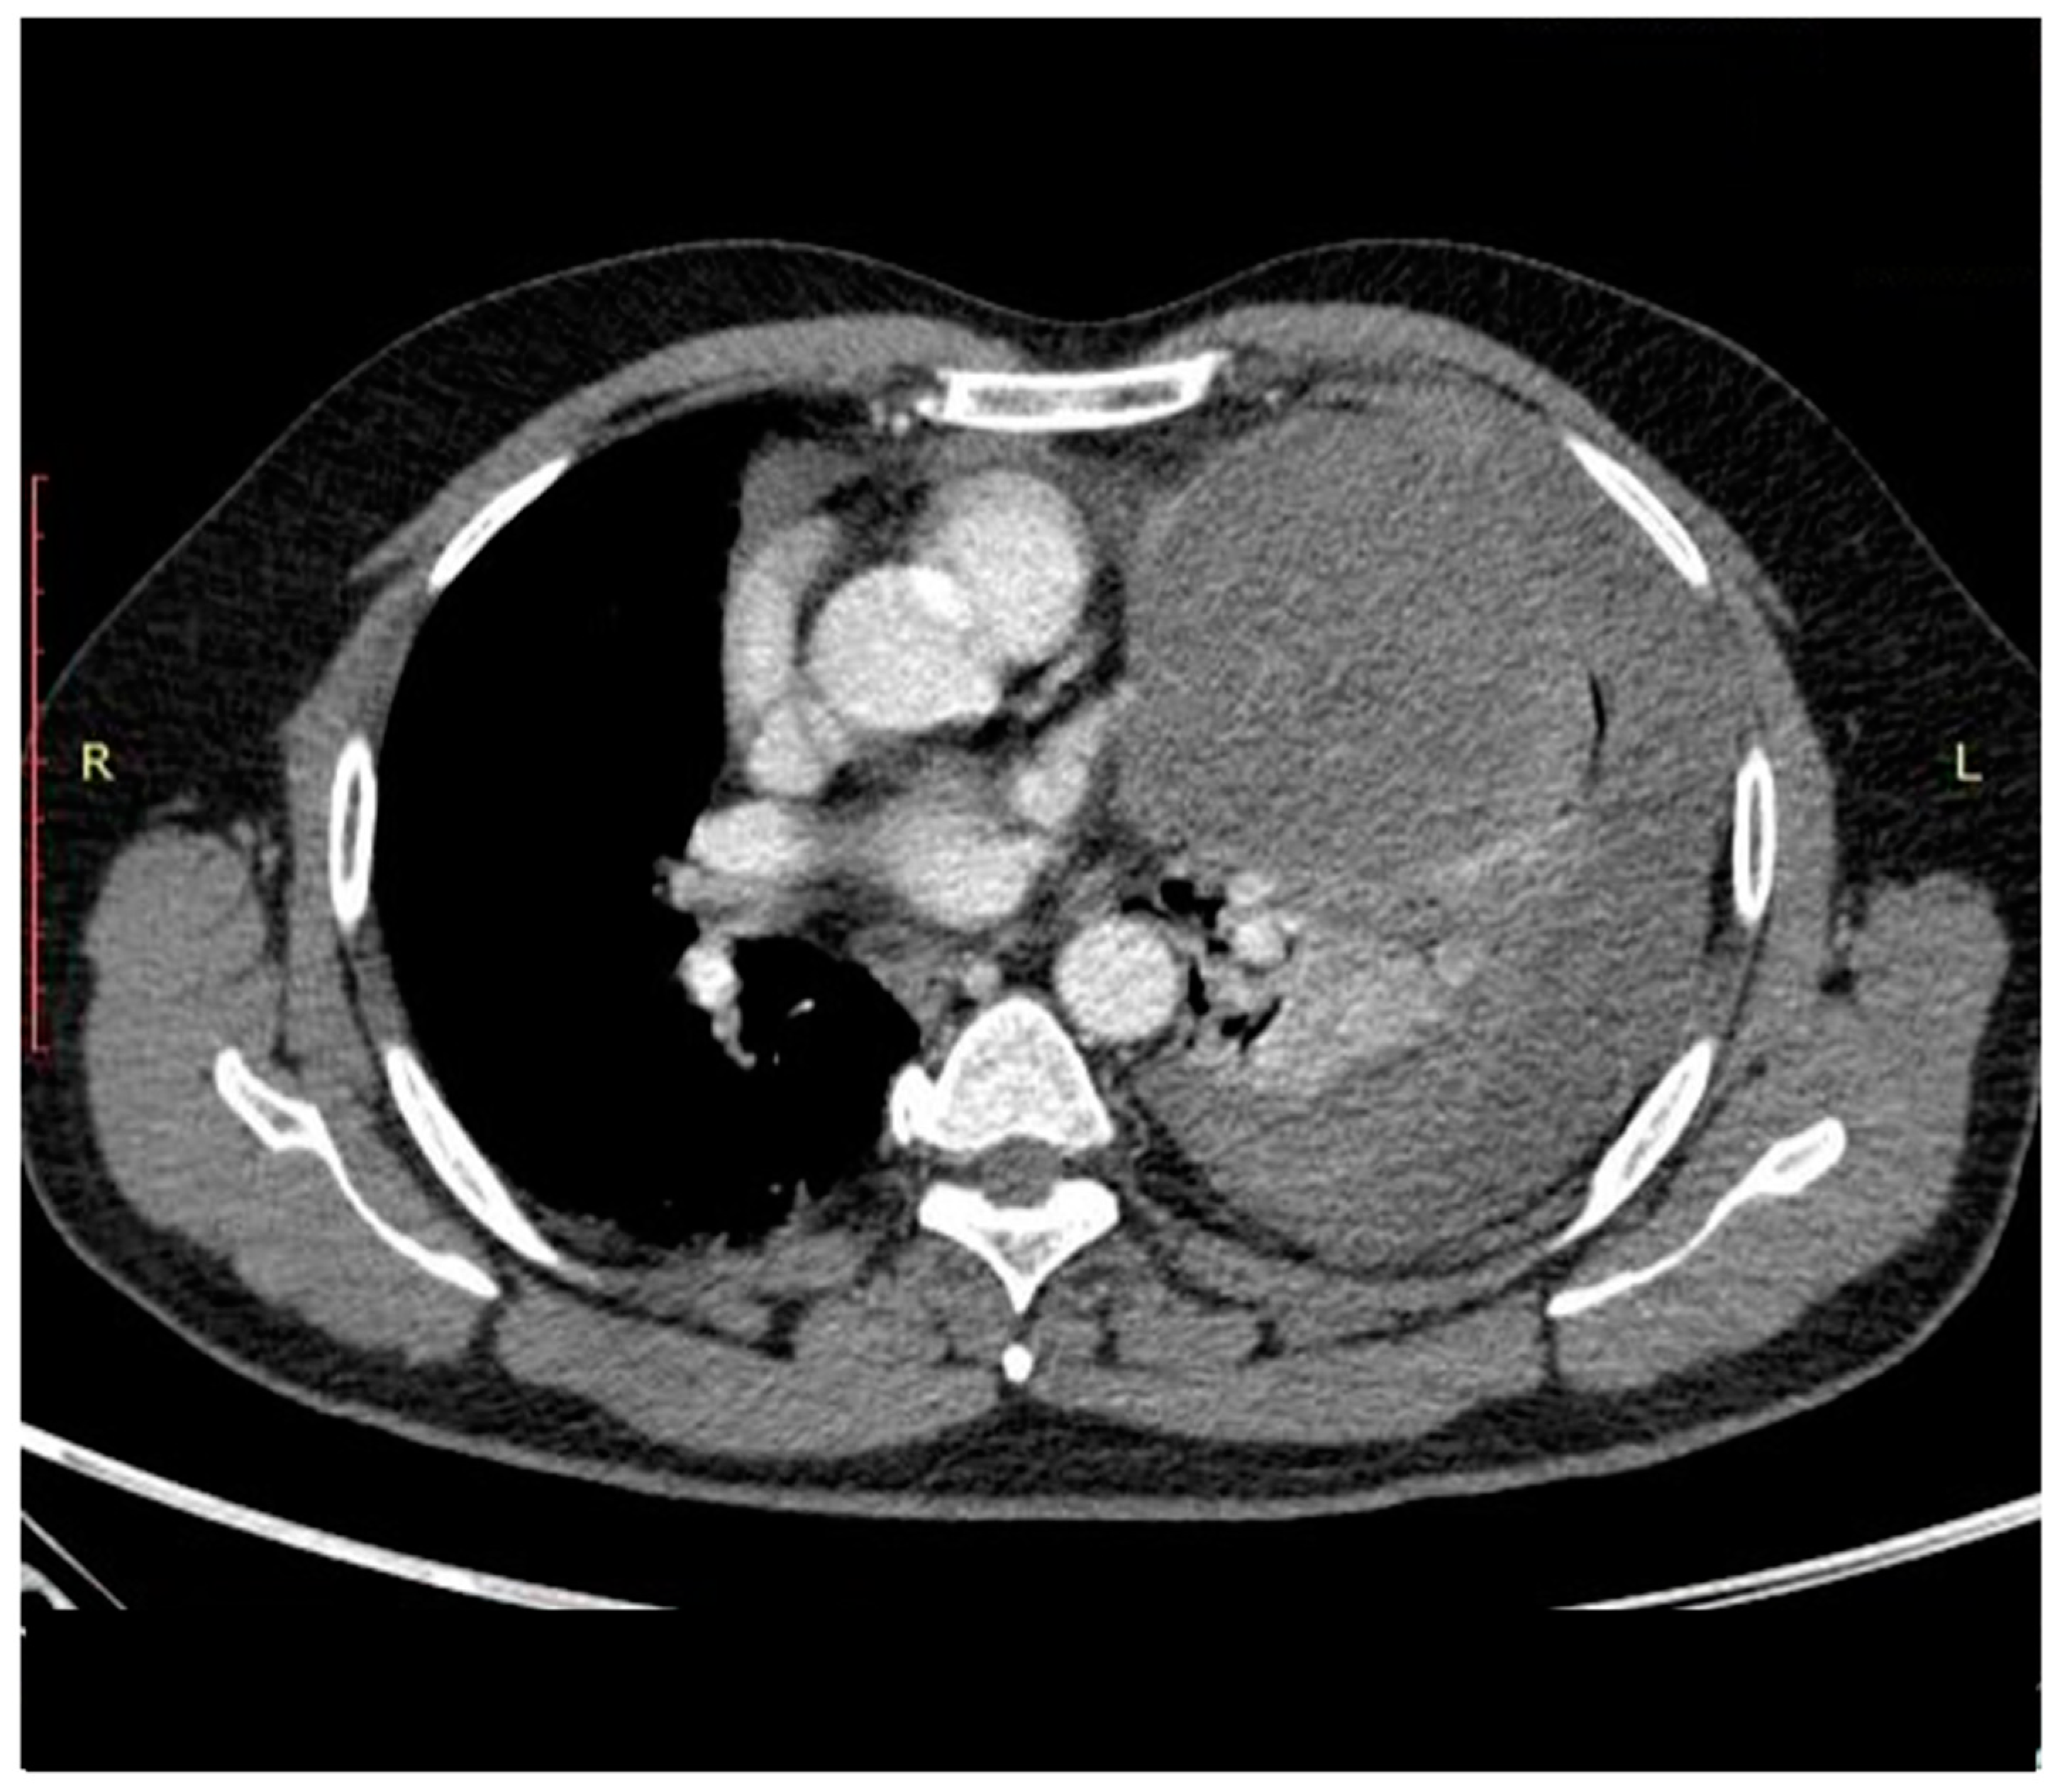

- Chaudhry, I.U.; Rahhal, M.; Khurshid, I.; Mutairi, H. Radical surgical resection for giant primary mediastinal endodermal sinus tumour with pulmonary metastasis after chemotherapy: Can be curative. BMJ Case Rep. 2014, 2014, bcr2014204662. [Google Scholar] [CrossRef]

- Liu, B.; Lin, G.; Liu, J.; Liu, H.; Shang, X.; Li, J. Primary mediastinal yolk sac tumor treated with platinum-based chemotherapy and extended resection: Report of seven cases. Thorac. Cancer 2018, 9, 491–494. [Google Scholar] [CrossRef] [PubMed]